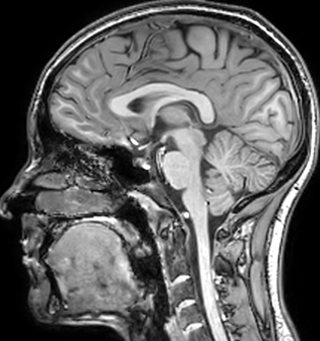

The techniques for measuring myelin have changed a lot over the years. “Since we are using the Elition, our myelin water images are much better. We're now acquiring 1 x 2 x 5 mm voxels and displaying at 1 x 1 x 2.5 mm. For a whole brain we can now measure the fraction of water in the myelin component in only about five or six minutes,” Dr. MacKay says.

of limiting MWI to the brain, even without the cerebellum, we can now spend about the same amount of time and scan the whole brain and the cervical spinal cord, which is a huge boost for us.” Dr. Rauscher says, “For MWI we perform 3D T2 with 32 or more echoes. This used to take a long time, but with Compressed SENSE we can decrease this to ten minutes for the whole head. Because of the large field of view (FOV) on the readout direction, we even get information from the brainstem, which we previously missed when we were using the GRASE approach. Having the whole head scan is nice because it has spatial resolution, orientation and FOV that are comparable to the standard 3D clinical MS scans, including the FLAIR and 3D T2, and a 3D T1 for brain volume.”

T1 - weighted

Myelin water imaging (echo 1)

With SENSE

With Compressed SENSE

Acquired resolution:

1 x 2 x 5 mm3

→

1.5 x 2 x 3 mm3

Number of echoes:

32 or 48

56

Echo spacing:

10 ms or 8 ms

7 ms

T1 - Weighted, Myelin Water Fraction Superimposed

Spinal cord coverage

Smaller, more isotropic voxels

Excellent detail in quantitative maps

Images courtesy of Adam Dvorak, Department of Physics and Astronomy, University of British Columbia

According to Dr. MacKay, MWI images benefit from Elition’s high quality gradients. “We need good gradients because we want to be able to do multi-echo sequences that have short TE times.”

Dr. Rauscher says, “With better gradients we can use a shorter echo spacing on the spin echo, so we get better sampling of the rapidly decaying myelin signal, which typically has T2 of around 10-20 milliseconds at 3 Tesla. If we can reduce echo spacing from about 8 to 5-6 milliseconds, we get a much better sampling of the short decay component and increase our SNR, which is a big advantage. The same is true for multi-echo gradient echo which we use for susceptibility mapping and for mapping venous vessels in MS.”